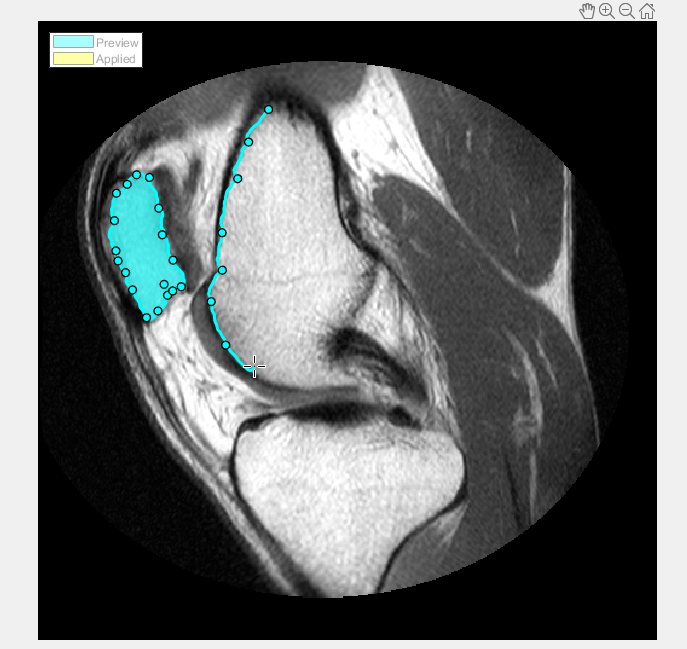

В данном примере считайте изображение в рабочую область. Этот пример использует изображение MRI колена. Цель состоит в том, чтобы создать рисунок маски, который сегментирует кость от мягкой ткани в изображении.

Выберите тип ROI, который вы хотите чертить. В данном примере выберите Assisted Freehand. Когда вы перемещаете курсор через изображение, он превращается в форму креста нитей. Нажмите кнопку мыши и начните чертить форму от руки по области изображения, которое вы хотите сегментировать. С опцией ROI От руки, которой Помогают, которая предварительно выобрана, можно чертить форму от руки, которая автоматически следует за ребрами в основном изображении, чтобы помочь вам чертить более точный ROI. Как вы чертите, щелкаете мышью, чтобы создать waypoints. Waypoints может помочь вам внести точные корректировки в форму после того, как вы закончите чертить. Чтобы добавить дополнительный waypoints после того, как вы закончите чертить, дважды кликните на ребре ROI.

Продолжите чертить формы до всех областей, которые вы хотите сегментировать, идентифицированы. Чтобы сохранить области ваш чертили, Нажмите Apply (их цветные изменения в желтом). Чтобы возвратиться к вкладке Segmentation, нажмите Close ROI.